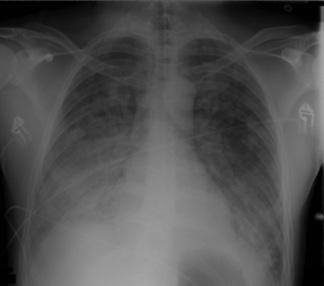

Rx: opacidades bilaterales que no se explican completamente por derrames, colapso lobular / pulmonar o nódulos en la radiografía de tórax o tomografía computarizada. Inicialmente alveolares que en segunda semana son mas intersticiales. Insuficiencia respiratoria que no se explica completamente por una insuficiencia cardíaca o una sobrecarga de líquidos (en ausencia de factores de riesgo de SDRA, se requiere una evaluación objetiva, como una ecocardiografía, para excluir estas causas de edema hidrostático).